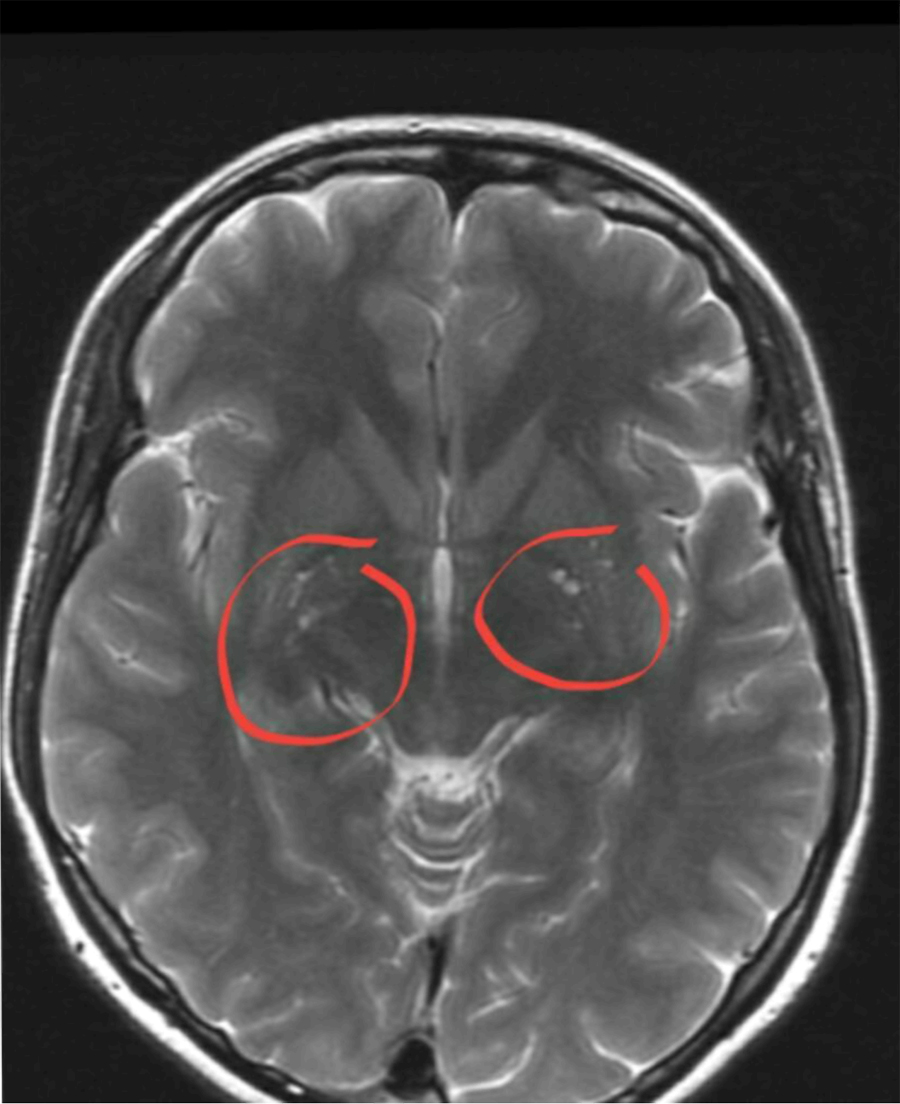

Хроническая ишемия головного мозга и лейкоареоз: симптомы и лечение